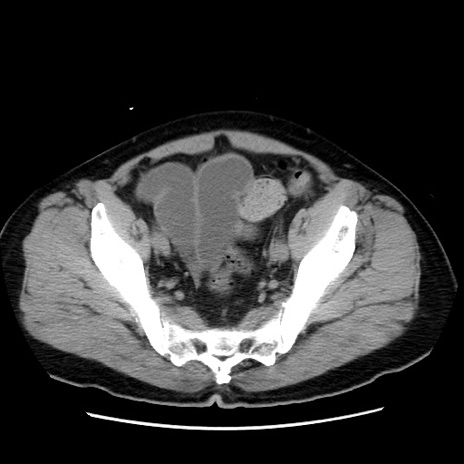

症例16(横断像)

【症例】 70歳代男性

【主訴】 腹痛、嘔吐

【現病歴】 約1ヶ月前より間欠的に腹痛と嘔吐あり、当院消化器内科を受診したところCTで多発する肝臓のLDAを指摘され、精査中であった。以降は消化器症状は安定していたが、2日前より嘔気と腹痛があり、同日より排便・排ガスが消失した。改善認めず、 本日、救急外来を受診した。

【既往歴】 大腸ポリープ切除後。

【身体所見】意識清明・会話良好、BT 36.3℃、BP 127/80mmHg、 P 80bpm、腹部:膨満あり、平坦・軟、上腹部正中および下腹部正中に圧痛あり、反跳痛なし、筋性防御なし。

【データ】WBC 7200、CRP 0.77